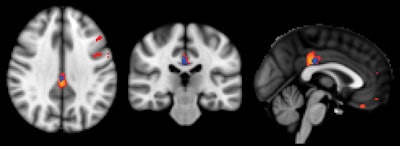

At the 18-month follow-up, the researchers found that 75 subjects had remained stable. The remaining 73 had deteriorated cognitively and also showed reduced perfusion in their ASL-MRI exams at baseline, particularly in the posterior cingulate cortex.

ASL-MRI showed decreased relative cerebral blood flow in the posterior cingulate cortex in subjects with deteriorated cognitive function versus those with stable cognitive function. Image courtesy of Radiology.Regarding the performance of ASL-MRI, the scan "simply prolongs an already existing MRI investigation for a few minutes without irradiation or contrast agent and is therefore minimally [disruptive] for the patients," Haller said. "Yet it provides complimentary information, which might help the early diagnosis of cognitive decline" and improve the identification of patients at risk, potentially leading to treatment that could slow or stop further decline.